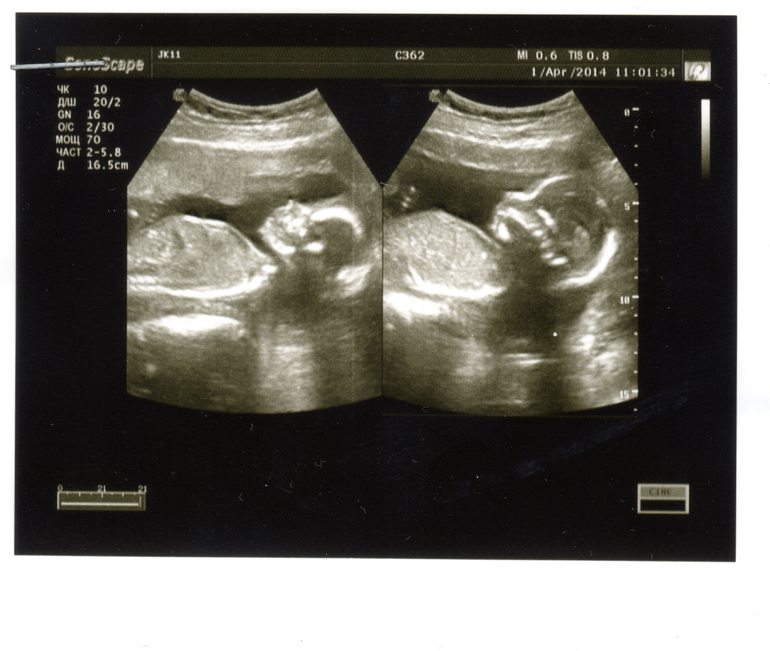

А у нас будет дочка!!

Такая стесняшка! на УЗИ все время отворачивалась от прибора и никак не хотела показывать писю ))) сложила ножки крестиком, пяточки под ягодицы поджала и ни с какой стороны было не видно. Полчаса ждали пока ножки раздвинет хоть чуточку  Дождались, когда я на бок повернулась. Врач дает 99% что девочка. До чего хорошенькая! Вся такая ровненькая, симметричная, пропорциональная! Наша доченька!

Дождались, когда я на бок повернулась. Врач дает 99% что девочка. До чего хорошенькая! Вся такая ровненькая, симметричная, пропорциональная! Наша доченька!